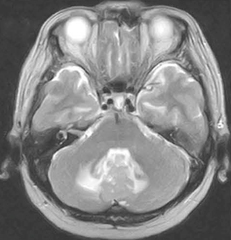

図3 第四脳室内髄膜種 67歳,女性。手術加療となった。 T2WI(脳ドック症例)

図3 第四脳室内髄膜種

67歳,女性。手術加療となった。

T2WI(脳ドック症例)